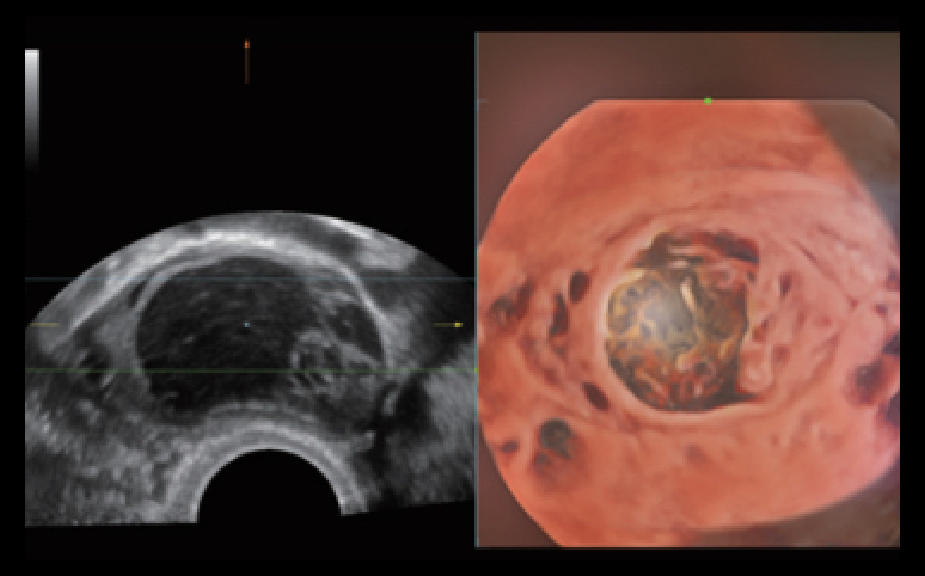

Clinical Images